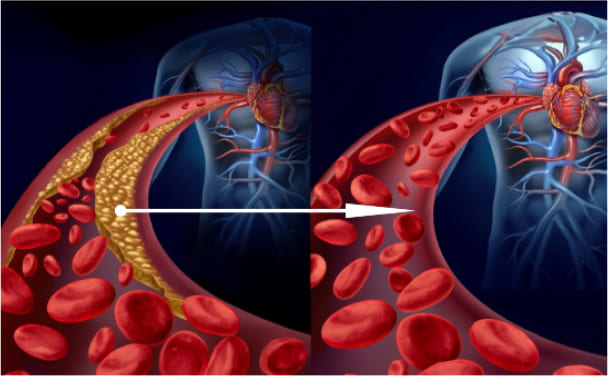

Ya, Anda benar. Plak kolesterol atau "plak aterosklerotik" menyumbang sekitar 65-70% dari kontaminasi vaskular.

Pada usia 50 tahun, hingga 5 kg plak kolesterol terakumulasi dalam pembuluh darah seseorang. Endapan kolesterol menyempitkan lumen pembuluh darah 4-5 kali.

Bayangkan. Jika lumen normal wadah adalah jari Anda, maka 5 kg plak kolesterol mengurangi lumen menjadi ukuran 4 korek api.

Plak kolesterol sendiri tidak mengancam jiwa. Ya, kualitas hidup menurun, tekanan meningkat, ada sakit kepala dan nyeri sendi, kelemahan, dan apatis. Yang jauh lebih berbahaya adalah massa trombotik dan kristal kalsium, yang juga terakumulasi dalam pembuluh darah kita.

Tensimin adalah campuran kapsul ekstrak tumbuhan. Saat dicampur dengan air, senyawa-senyawa ini aktif. Agen-agen ini membantu membersihkan kolesterol, gumpalan darah (plak kalsium), dan sisa-sisa obat dari pembuluh darah, memastikan aliran darah yang lancar.

Dalam satu setengah bulan, Tensimin melarutkan dan menghilangkan 4 kg plak kolesterol, menipiskan massa trombus 900 gram hingga 1 kg, dan menghilangkan 350-400 gram kristal kalsium.